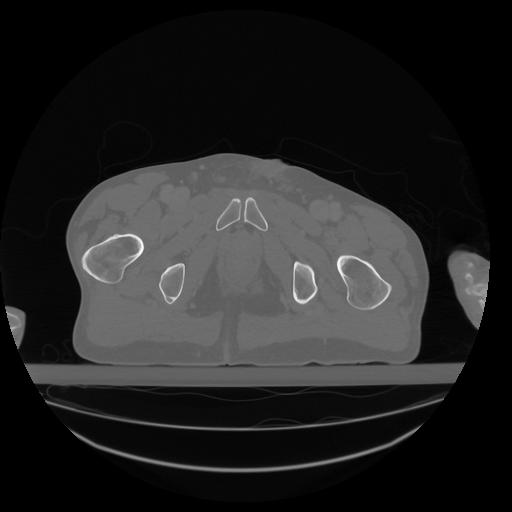

34 CUERPO,CE,Vol,1.0,CUERPO,,